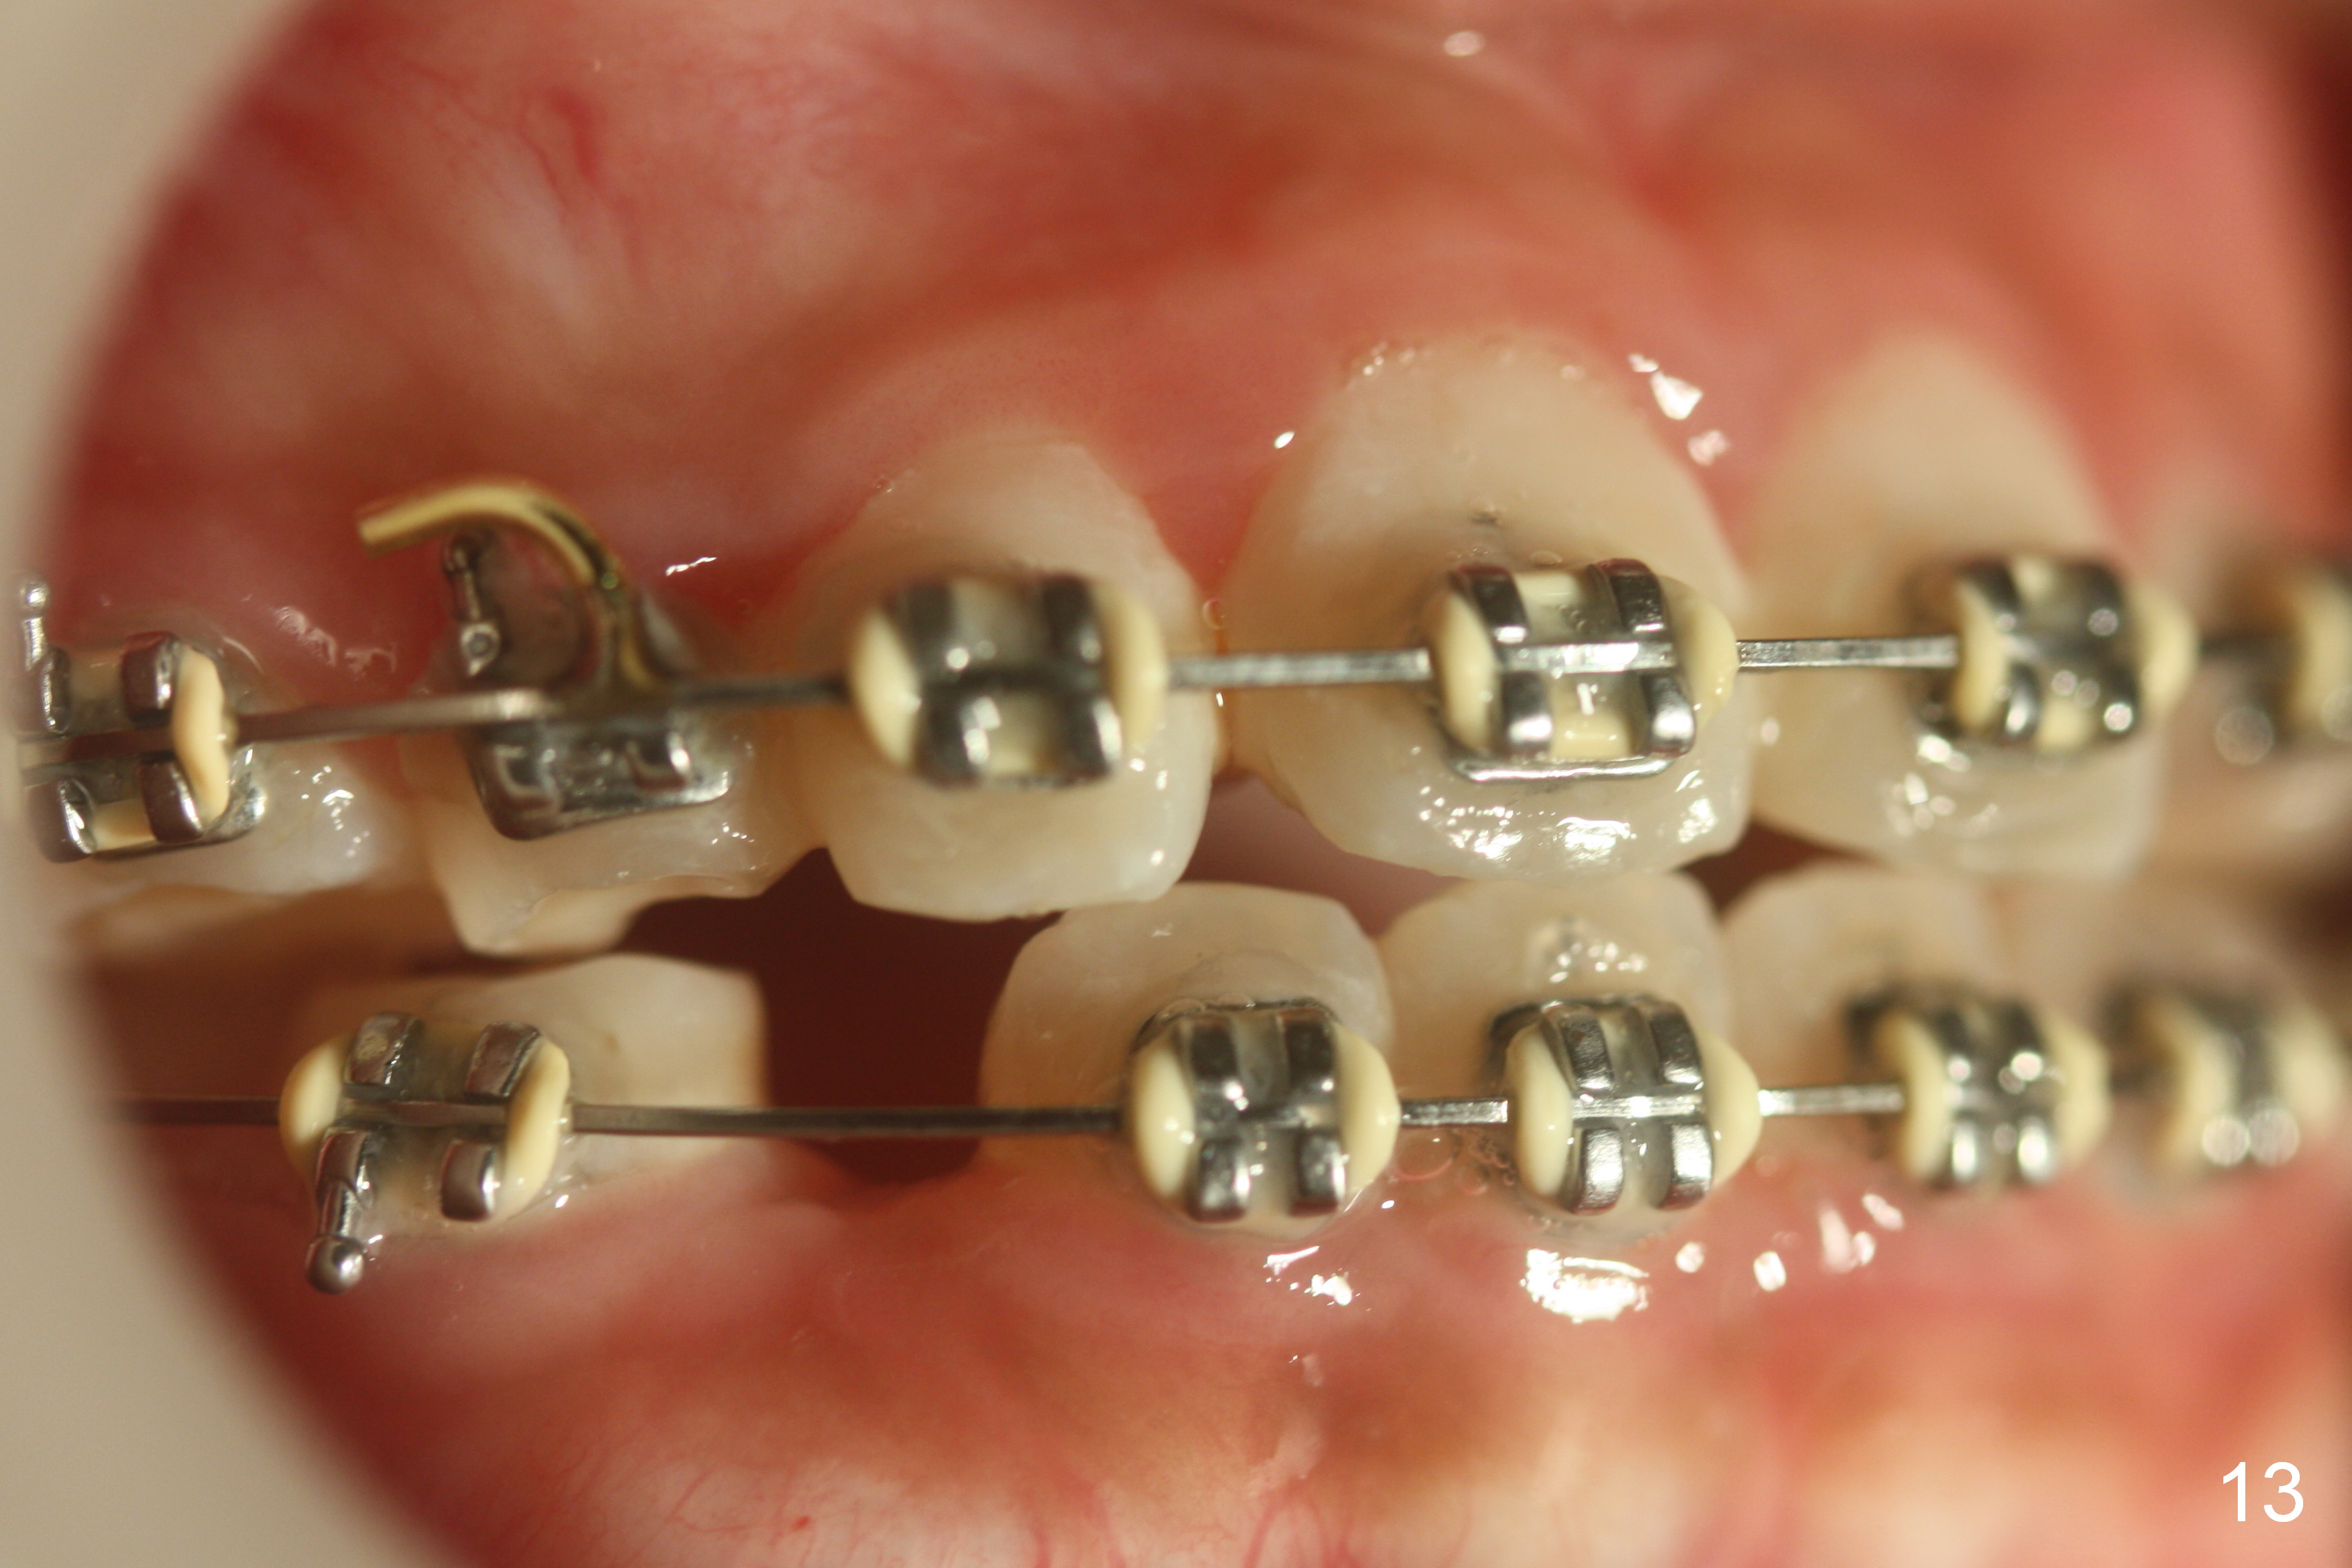

OK Xin, just evaluated the case. If she started with the anterior dental crossbite and you are barely over-corrected right now, I would be very comfortable discontinuing treatment. At her age, there is nothing that can no longer be dealt with beautifully when it is more age appropriate.When anterior cross bite is corrected 19 months post banding, the tooth #10 (microdontia) has tendency of edge-to-edge (Fig.16,17). Power chains are used to create space for #11 to erupt fully before bracketing. In spite of the effort, the peg lateral remains edge-to-edge 23 months post banding (Fig.18,19). The segmental 19x26 braided wire retains as a retainer to prevent #10 from cross bite. The facial profile is more or less normal immediately post debracketing (Fig.20). The anterior occlusion appears to remain basically the same 7 months post debracketing (Fig.21,22). UR3 erupts, while the diastema mesial to UL2 enlarges so that the arch wire appears shorter. UL2,3 appear to be in cross bite 14 months post debracketing, while Es retain at the age of 13 (delayed development, Fig.23).